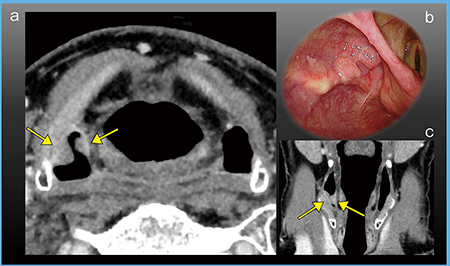

症例1は右の梨状陥凹に隆起性病変があり,内視鏡的に下咽頭がんと診断された症例である。Aquilion Precisionでは,6mmと5mmの隆起性病変が2か所,明瞭に描出されている(図5)。

図5 症例1:下咽頭がん(T1)

a:超高精細CT(1mm厚,AIDR 3D) b:内視鏡画像

c:超高精細CT(コロナル画像,2mm厚)